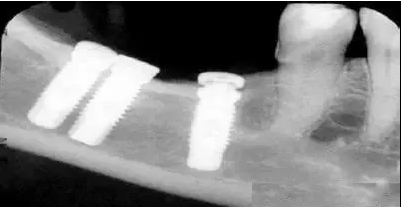

2.異物偽影:主要為密度差別極大的物體如金屬和人體組織一起掃描時所造成,偽影的特點是沿著高密度物體呈放射狀排列。有時圖像上不一定能直接看到目標異物,但只要仔細觀察偽影的放射狀搏列方向,即能找到異物的來源。

2、金屬異物偽影:金屬異物產(chǎn)生的放射狀偽影,嚴重時明顯影響診斷。在掃描前應(yīng)去除病人體外隨帶的金屬物質(zhì),而病人體內(nèi)無法去除的金屬物質(zhì),如假牙或牙內(nèi)填充物、假肢、各類金屬支架等,可采用傾斜機架或掃描線的角度盡可能避開。目前也有研究采用某種算法抑制此類偽影。腹部常規(guī)掃描一般服溫開水,盡量不要服含碘造影劑。